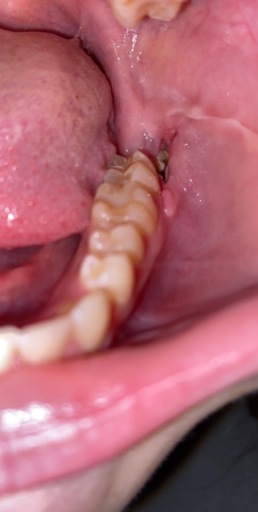

Is this an infection?

I just had all 4 wisdom teeth removed 3 days ago and this is on the bottom left side and I can’t tell what it is. It is only on the left bottom side and from trying to look it up on the internet I can’t tell if it’s an infection or not.